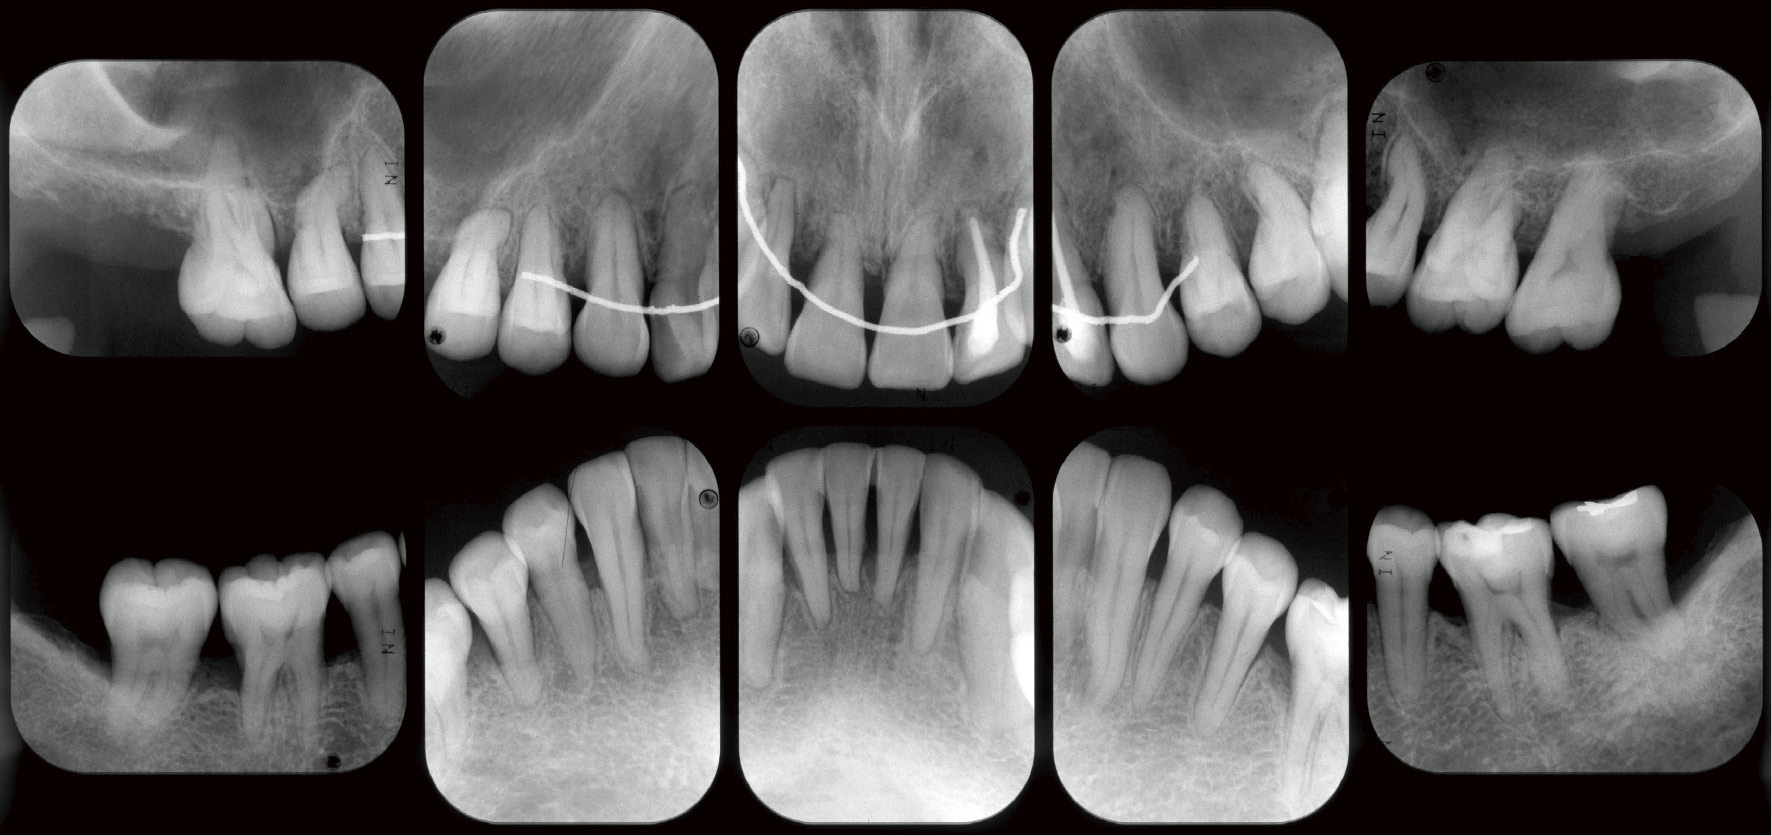

再評価時デンタルエックス線写真

歯周―矯正終了時デンタルエックス線写真

SPT移行時 デンタルエックス線写真

2016年 SPT時デンタルエックス線写真